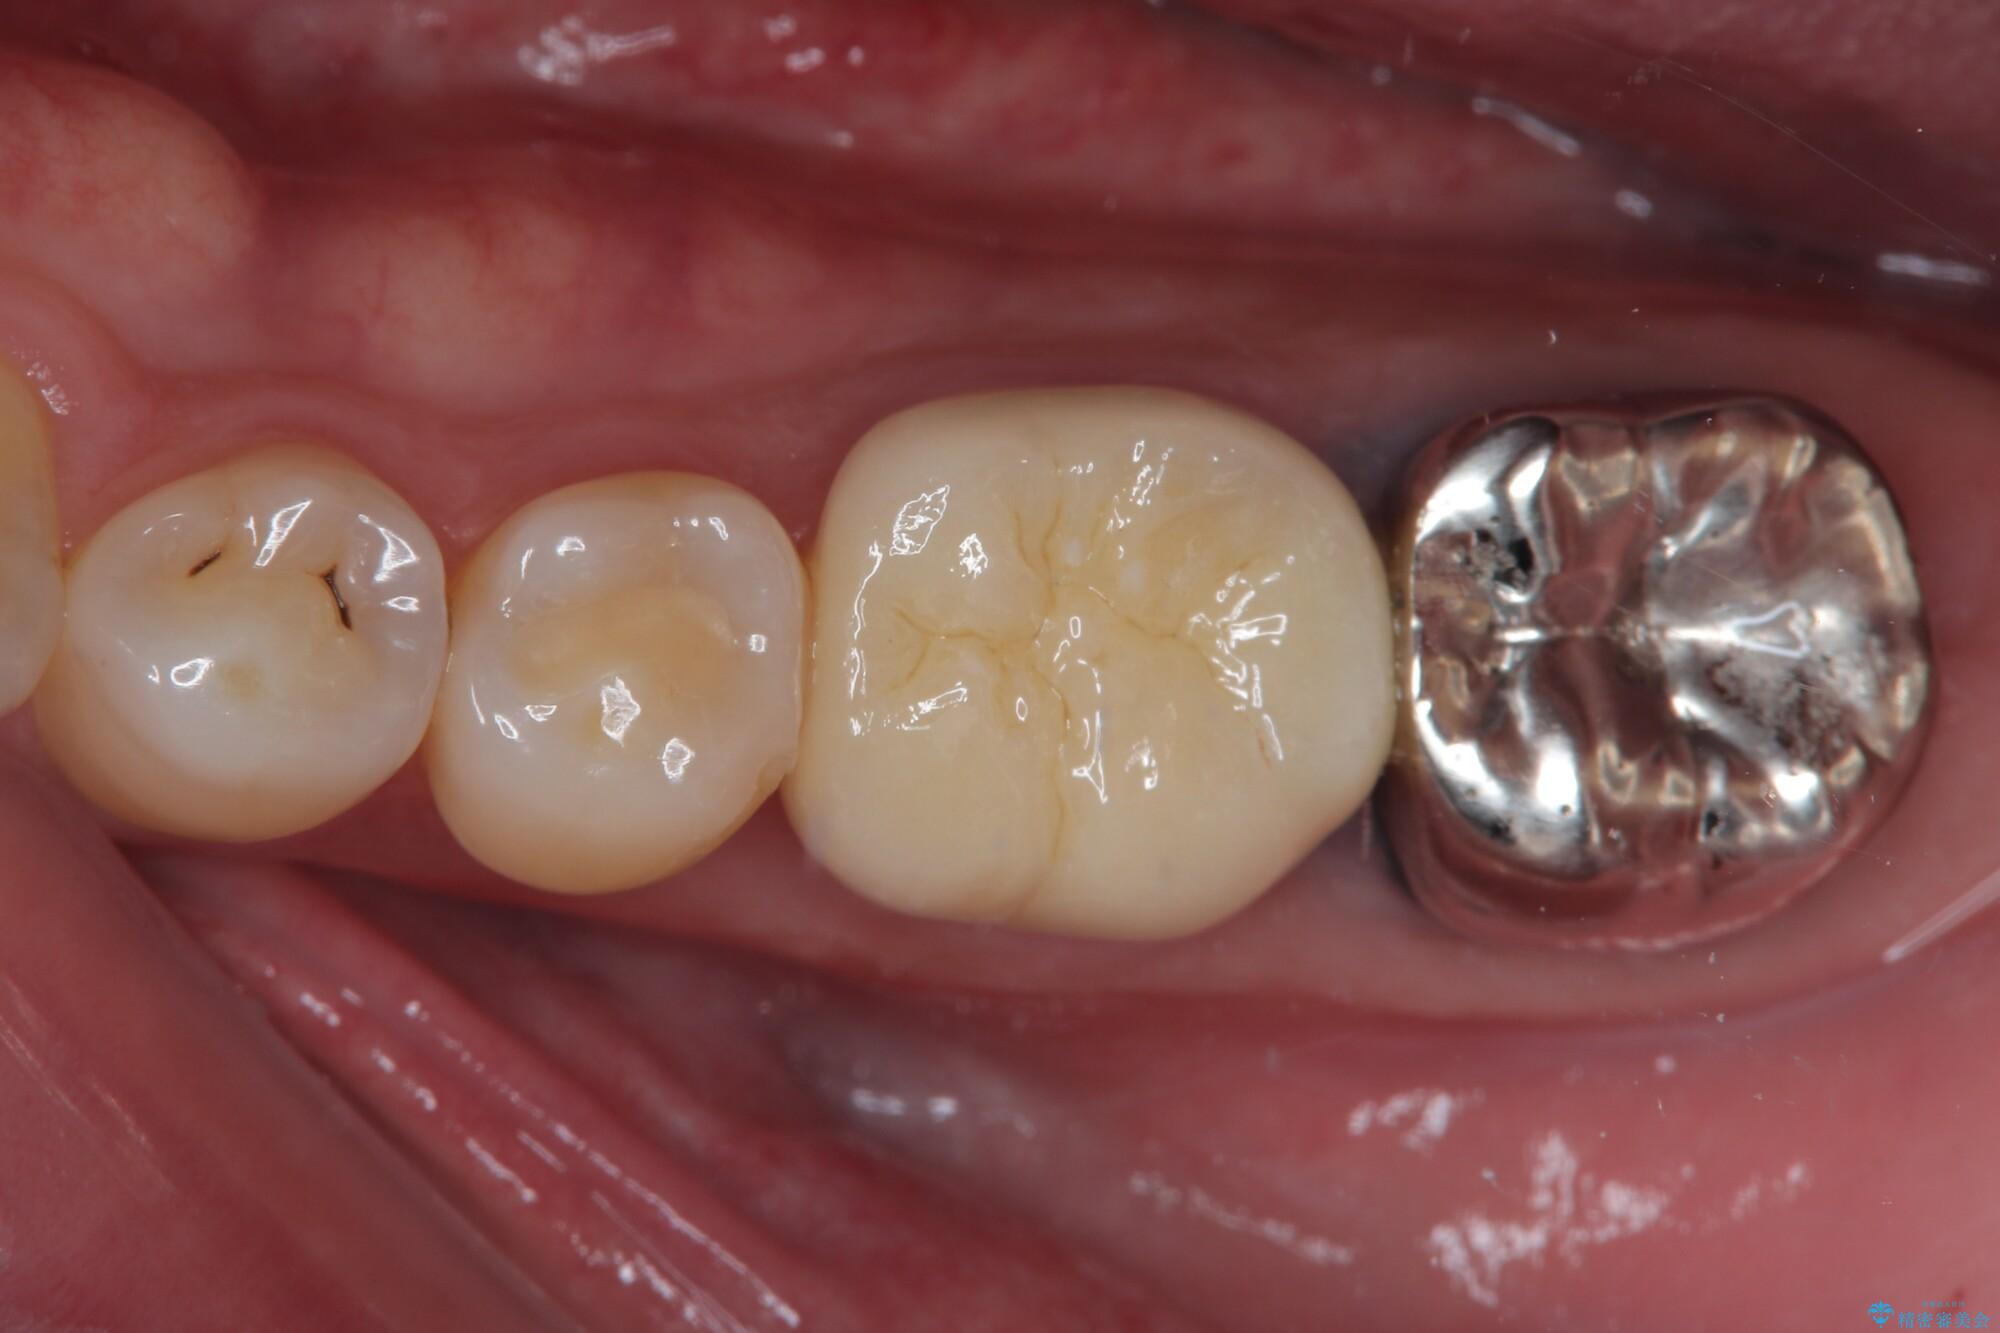

- 下顎大臼歯が噛めないほどの痛みを感じるとのことで来院された患者様です。

レントゲン写真などで診査を行ったところ、不適合な詰め物の周りから炎症が波及し、神経組織が壊死していると診断されました。

まずは根管治療を行い、症状が消退したことを確認してオールセラミッククラウンにて補綴治療を行うこととしました。

根管治療を行った奥歯は、再発防止や残された歯質を守るため、クラウンによる補綴治療が必要となります。